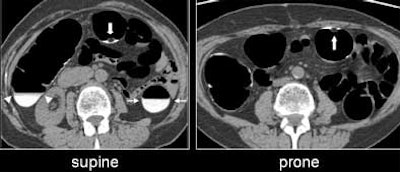

| Untagged stool can be seen floating in a small pool of barium (large white arrow, right and left). Well-tagged fluid in the descending (small white arrows) and the ascending (white arrowheads) colon. All images courtesy of Dr. Hiro Yoshida. |